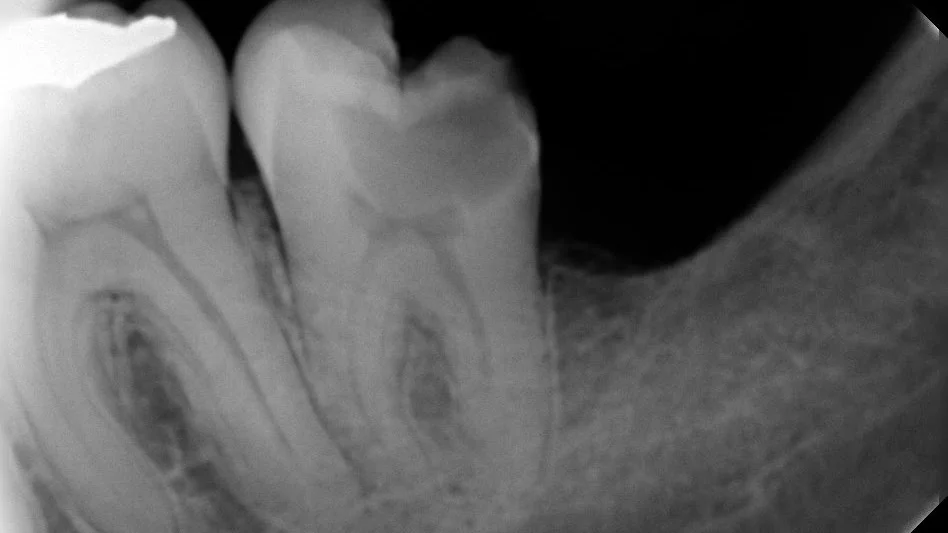

La endodoncia, también conocida como tratamiento de conductos, es un procedimiento que se realiza cuando el nervio del diente está dañado o infectado. Su objetivo es aliviar el dolor, limpiar el interior del diente y conservar la pieza en boca.

Posteriormente se anestesia, se aísla el diente y se limpian los conductos con limas endodónticas y líquidos antisépticos. Finalmente se rellena con un material estéril llamado gutapercha. ¡Y listo!